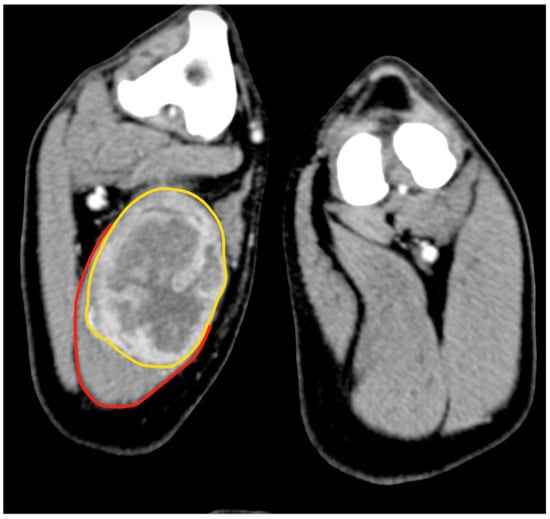

An 11.5-year-old, 28 kg, castrated male Labrador retriever was referred for a 4 cm painless, firm mass in the caudal region of the thigh. The mass had been present for several months but had recently grown. The dog showed no lameness or discomfort. Physical examination and the laboratory profile (complete blood count—CBC, biochemical values and urinalysis) were unremarkable. An incisional punch biopsy was performed during the total body CT exam (Figure 1). The histology was compatible with a soft tissue sarcoma showing chondromyxoid differentiation.

Figure 1.

Tomographic appearance of the neoplasm within the semitendinous muscle. The yellow line delimitates the mass, and the red line is the semitendineous muscle. Orientation: cranial is on the top of the figure.

Cytology of the lesion via fine needle aspiration (FNA) was not diagnostic; therefore, an incisional biopsy was performed at the time of the total body CT. This revealed a 5.8 cm × 5.5 cm, poorly defined mass confined within the biceps femoris muscle, with heterogeneous enhancement after the administration of an intravenous contrast medium (Figure 2). No lesions suggestive of metastatic spread were observed. The histology from the bioptic sample was morphologically suggestive of PWT.

Figure 2.

Tomographic appearance of the sarcoma within the biceps femoris muscle, axial view (A). The yellow line delimitates the tumours, the red line the biceps muscle 3D reconstruction, and the white arrow indicates the tumour (B).